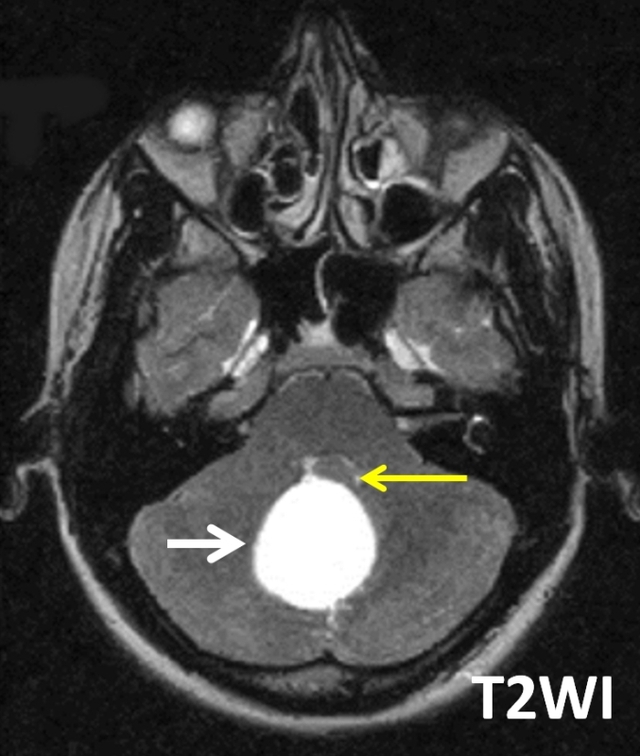

患者女性,29岁,头痛、视物模糊和共济失调。

答案:A. Blake囊肿

Blake囊肿是一种后颅窝的小蛛网膜囊肿畸形,被认为是继发于第四脑室正中孔形成障碍的Blake小袋退化失败所致髓帆向小脑延髓池的囊性扩张。

Blake囊肿经典的影像学表现有后颅窝小脑蚓部(图中黄色箭头)后下方可见一装满脑脊液的囊肿(图中白色箭头),该囊肿后方与小脑延髓池(图中红色箭头)分离。该病例中未见小脑蚓部发育异常,而Dandy-Walker综合征这常伴小脑蚓部发育不全。